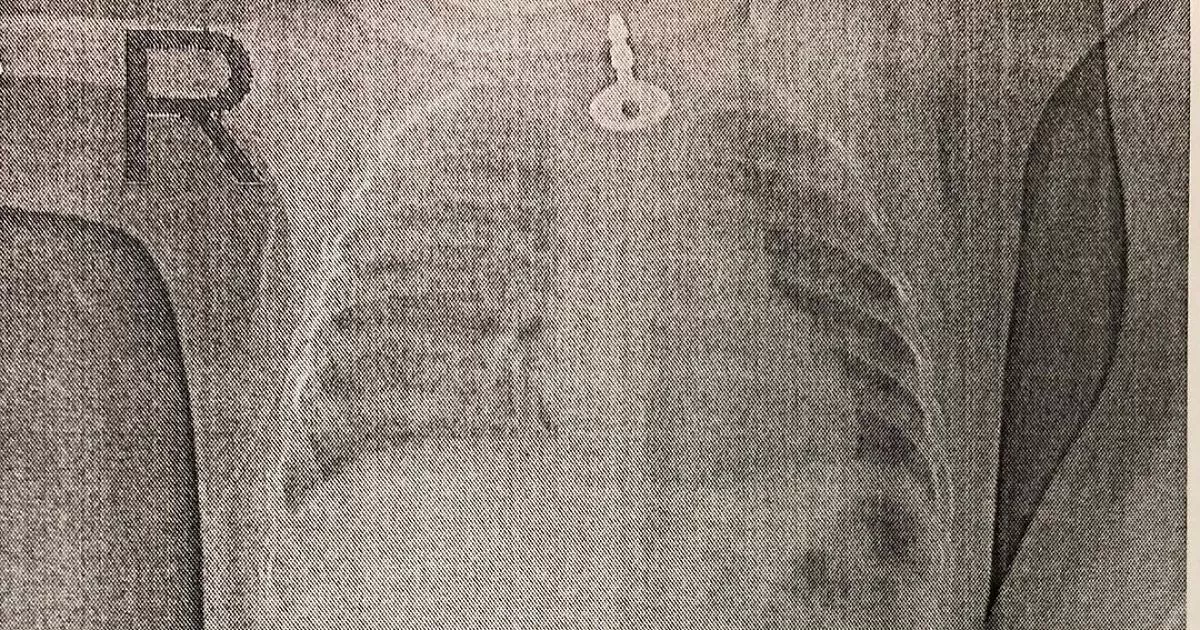

- Ключ на снимке застрял в верхнем сужении пищевода. Пришлось повозиться, но в итоге ключ достали, - уточнил доктор.